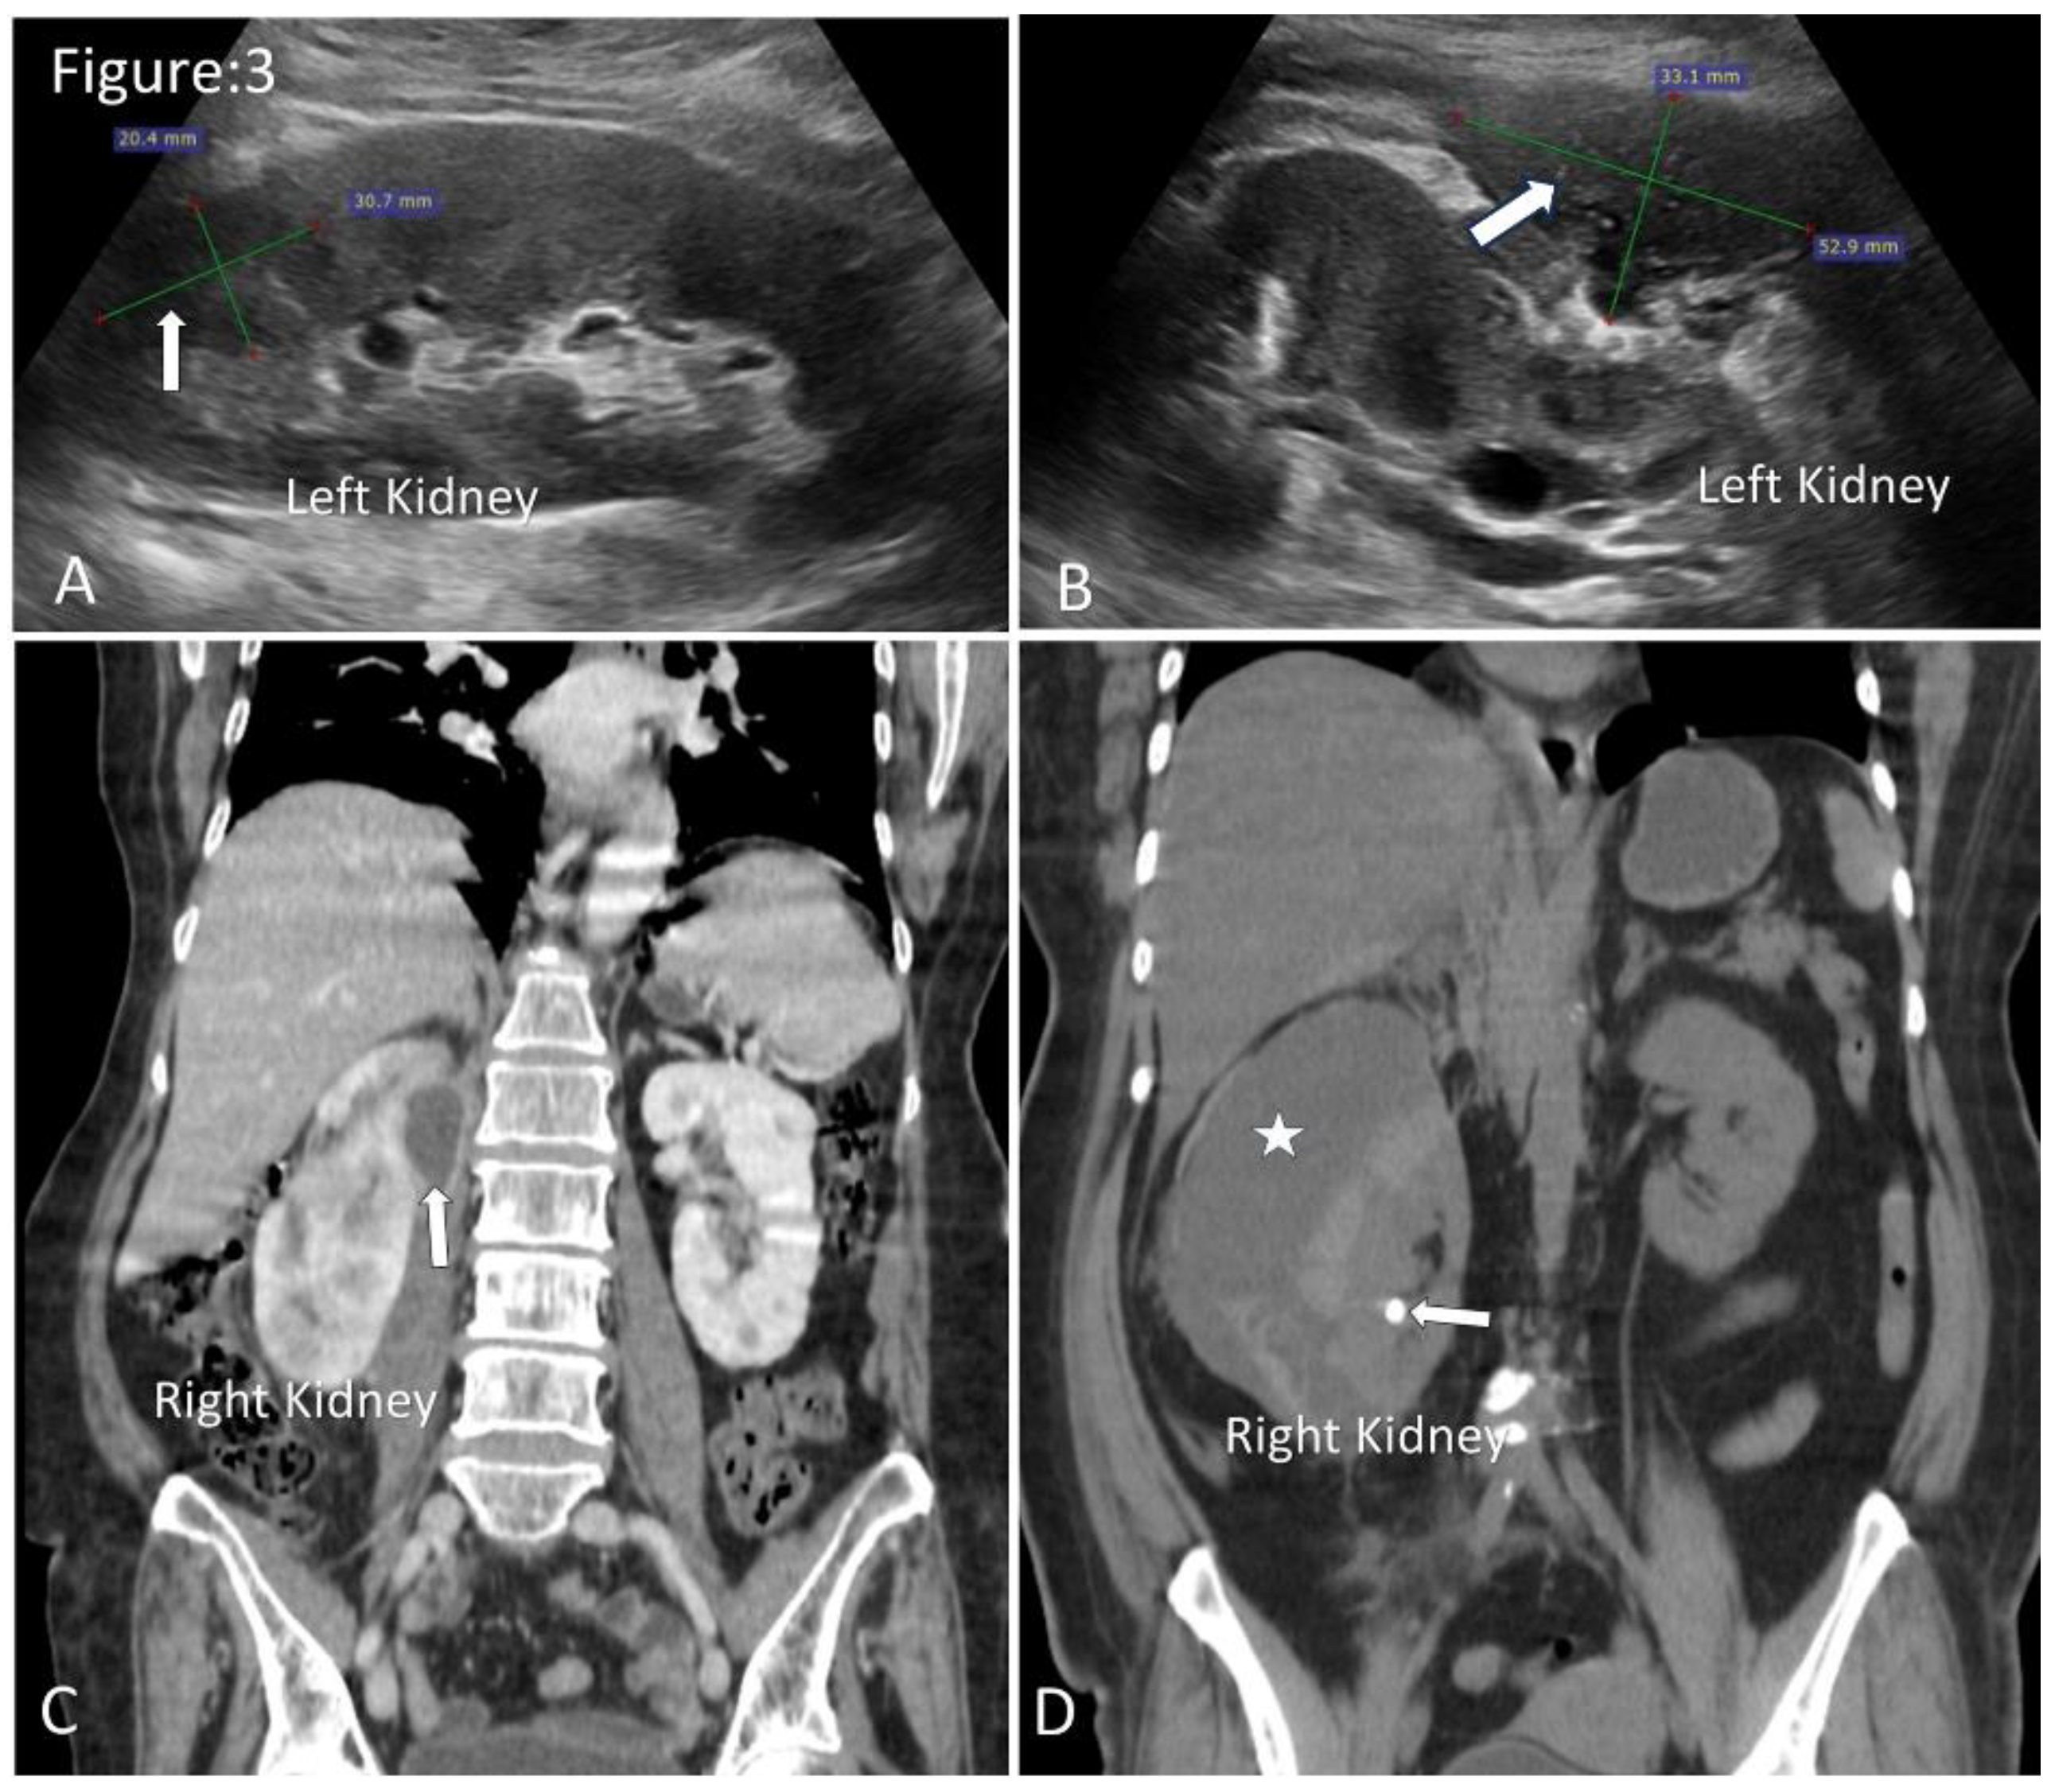

Renal and Perinephric Abscesses

- Gardiner, R.A.; Gwynne, R.A.; Roberts, S.A. Perinephric abscess. BJU International, 2011; 107, 20–23. [Google Scholar] [CrossRef]

- Liu, X.-Q.; Wang, C.-C.; Liu, Y.-B.; Liu, K. Renal and perinephric abscesses in West China Hospital: 10-year retrospective-descriptive study. World Journal of Nephrology 2016, 5, 108–114. [Google Scholar] [CrossRef]

- Rubilotta, E.; Balzarro, M.; Lacola, V.; Sarti, A.; Porcaro, A.B.; Artibani, W. Current Clinical Management of Renal and Perinephric Abscesses: A Literature Review. Urologia Journal. 2014, 81, 144–147. [Google Scholar] [CrossRef]

- Zhang, X.; Xie, Y.; Huang, G.; Fu, H. Analysis of 17 children with renal abscess. International Journal of Clinical and Experimental Pathology 2019, 12, 3179–3184 PMID: 31934162. [Google Scholar] [PubMed]

- Bhatt, S.; MacLennan, G.; Dogra, V. Renal Pseudotumors. American Journal of Roentgenology. 2007, 188, 1380–1387 . [Google Scholar] [CrossRef]

- El-Ghar, M.A.; Farg, H.; Sharaf, D.E.; El-Diasty, T. CT and MRI in Urinary Tract Infections: A Spectrum of Different Imaging Findings. Medicina. 2021, 57, 32 . [Google Scholar] [CrossRef]